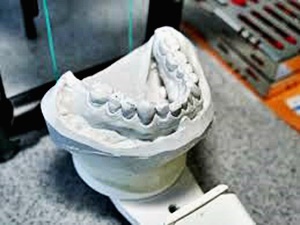

사랑니란?

우리가 사랑니라고 부르는 것은 큰 어금니 중 세 번째 위치에서 제일 마지막에 나오는 치아입니다. 사랑니가 나올 때에는 첫사랑을 하듯이 아프다고 하여 붙여진 이름이라고 하는데요. 다른 이름으로는 ‘지치’라고 합니다. 지치는 사리를 분별할 수 있는 지혜가 생긴다는 뜻입니다.

사랑니는 보통 큰 어금니와 비슷하게 생겼습니다. 사랑니의 형태나 크기는 매우 다양하다고 하는데요. 보통의 어금니 보다 깊이 나기 때문에 빼기 어렵거나 절개를 통해 힘들게 빼야 하는 경우가 많습니다. 원래 사랑니는 음식물을 갈아 내기 위한 용도라고 하는데요. 이것은 치아의 퇴화 현상이라고 생각하시는 분들도 많이 계십니다.